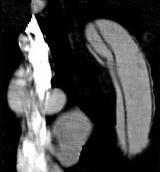

问题 请看一组主动脉的CT增强图像,正确的描述和结论是 ( )

选项 A、真腔较假腔小 B、真假腔之间线状低密度影为内膜片影 C、主动脉瘤 D、主动脉夹层 E、主动脉血栓

答案 ABD